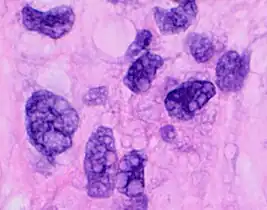

Pleomorphic when having different sizes and shapes. This often correlates with an increased nucleus to cytoplasm ratio. These features generally indicate malignancy.

Subcellular features (may need highest magnification)